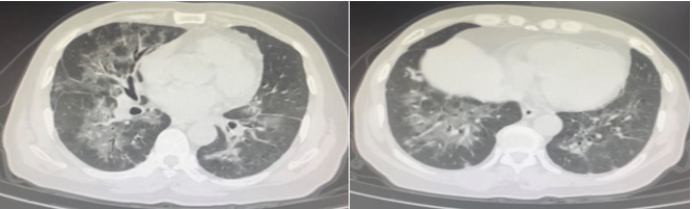

治疗2天后带患者外出做头胸部CT:考虑左侧枕叶脑出血(图5),建议短期复查除外其他;双肺磨玻璃影伴斑片影,考虑多发感染(图6)

图片

图5 头部CT(2023-02-03)

图6  胸部CT(2023-02-03)